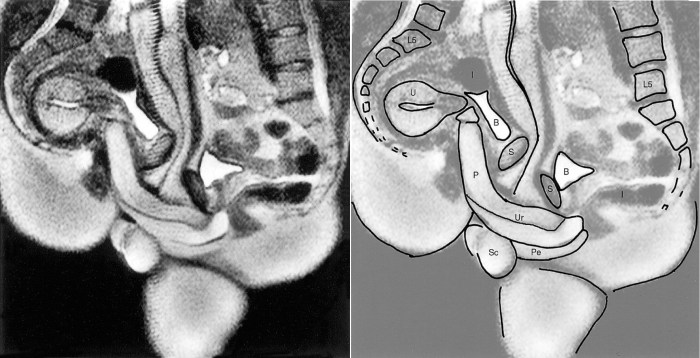

MRI Skill Picture